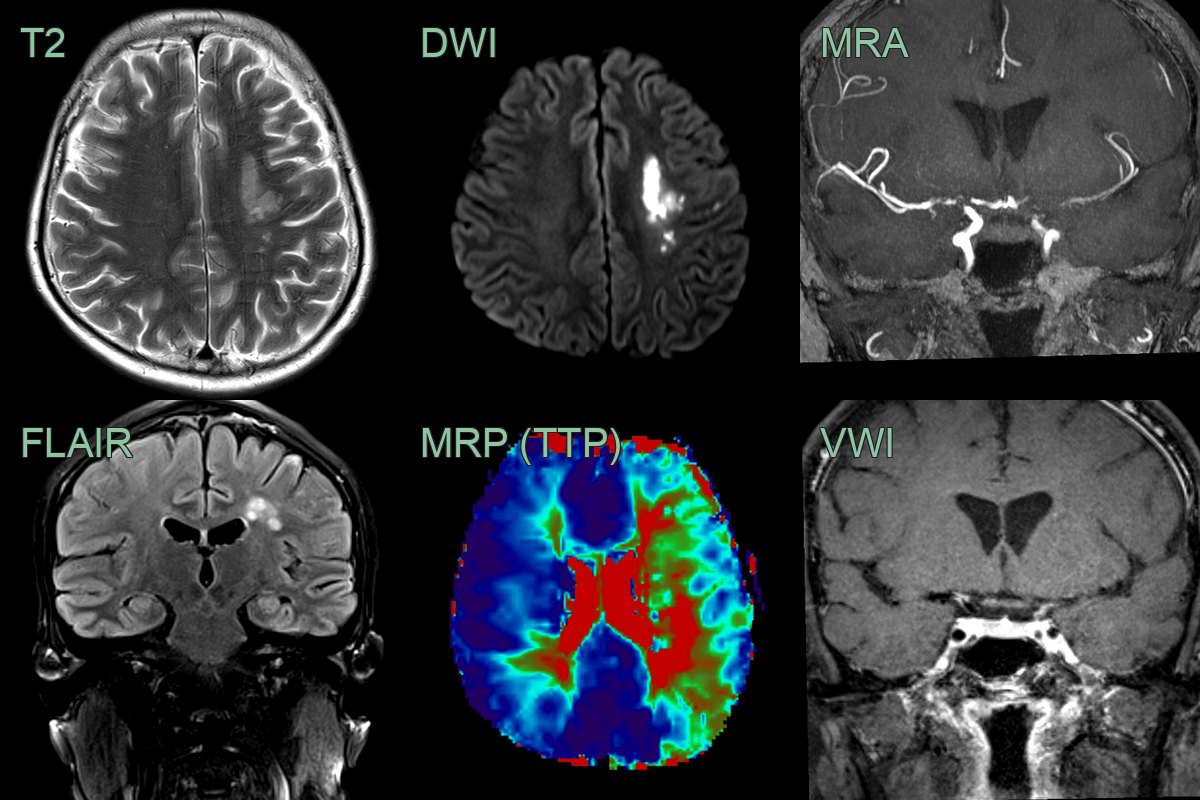

- A 35-year-old patient presenting with photophobia and headache was diagnosed with HIV with a CD40 count of 80.

- Baseline MRI showed an old infarct in the left thalamus. VWI imaging showed concentric enhancement within stenosis in the terminal ICA and MCA.

- Over the following 4-6 weeks, the mural enhancement was static. The stenoses only minimally progressed but the perfusion to the left and, to a lesser extent, right cerebral hemisphere worsened.

- With worsening perfusion, an angioplasty successfully widened the stenosis and significantly improved perfusion.